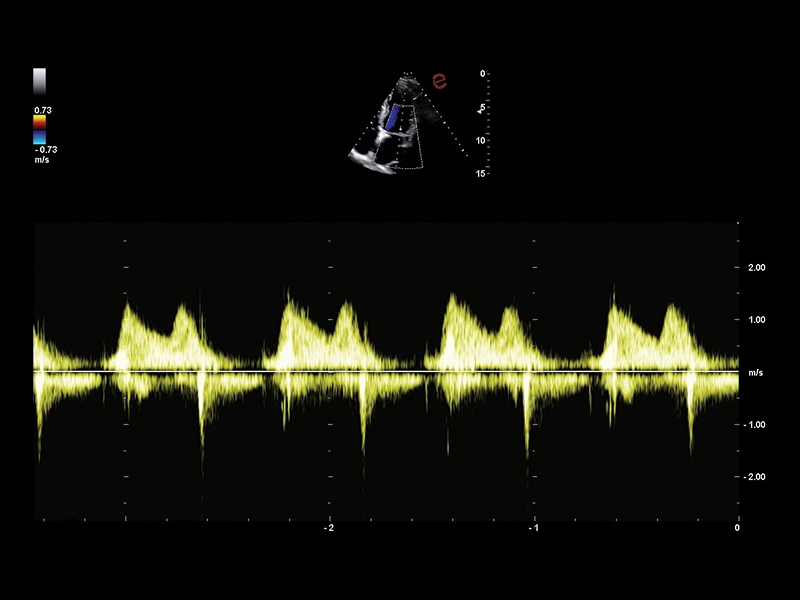

MyLab™C30 - Doppler - CW

MyLab™C30 - Doppler - CW